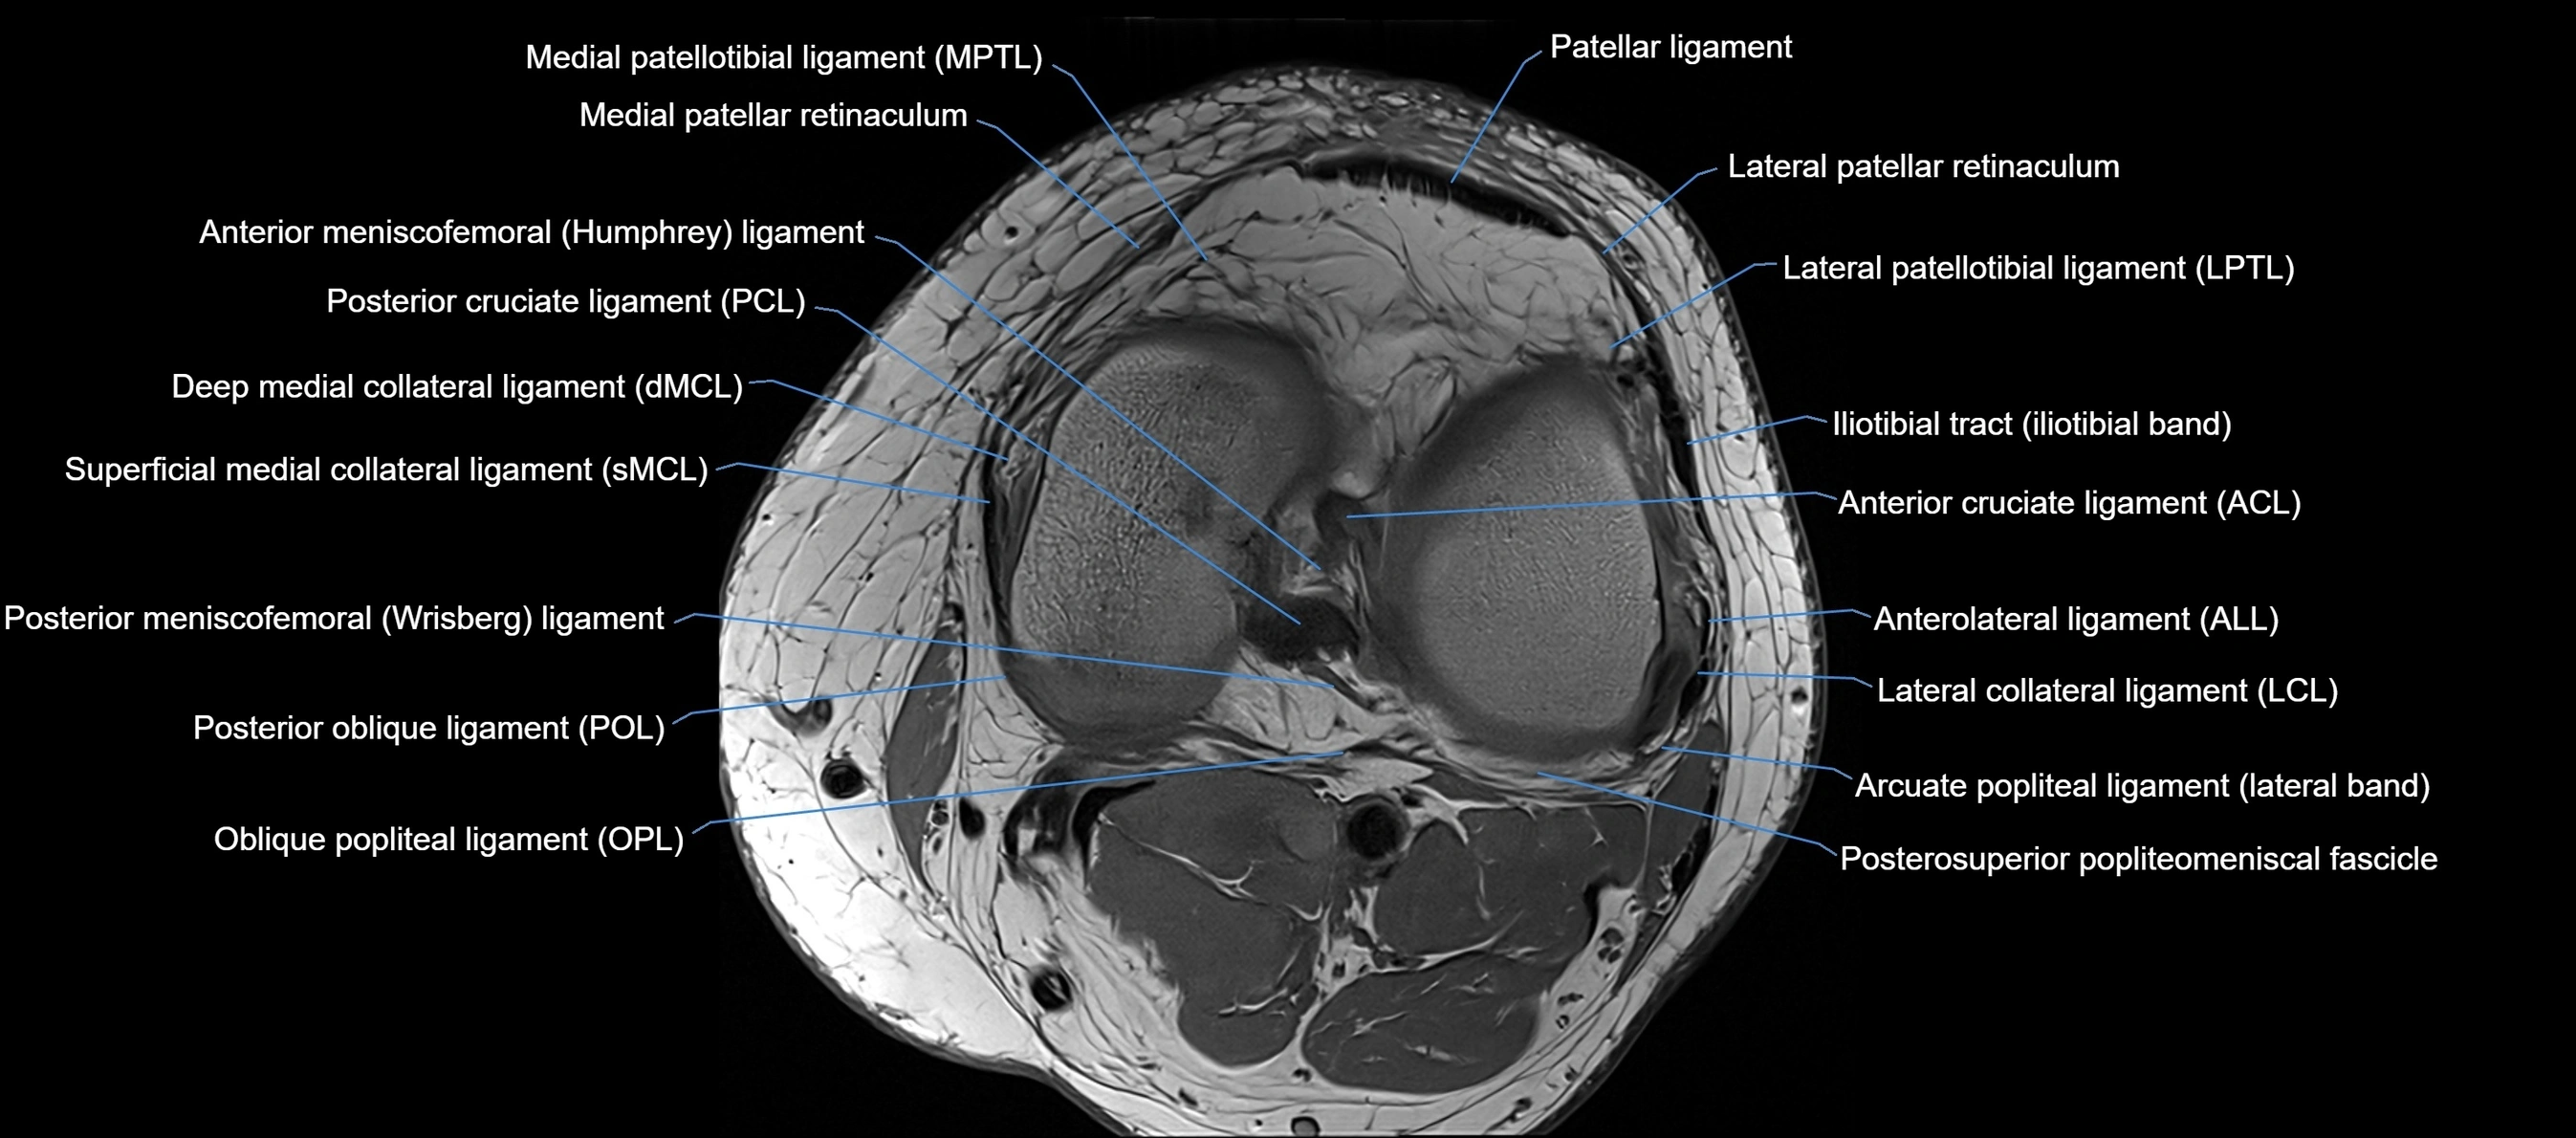

MRI Appearance

T1-weighted images:

• Normal ACL appears as a low-signal band-like structure crossing the intercondylar notch

• Surrounded by intermediate signal synovial fluid and fat planes

T2-weighted images:

• Normal ACL remains low signal

• Partial or complete tears appear as discontinuity, increased signal, or fiber laxity

MRI images

image